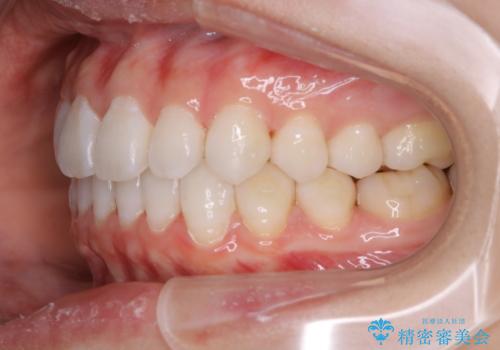

インビザラインで矯正治療中に、クリーニングを行ったbeforeafter写真です。

矯正治療中は、虫歯や歯周病のリスクが高くなったり、長い時間マウスピースを着用することにより、ステイン(着色)がしやすくなることがあります。

そのため矯正治療中は、(マウスピース矯正・ワイヤー矯正共に)クリーニングを行い、こまめに汚れを取り除き、お口のケアをすることが大切です。